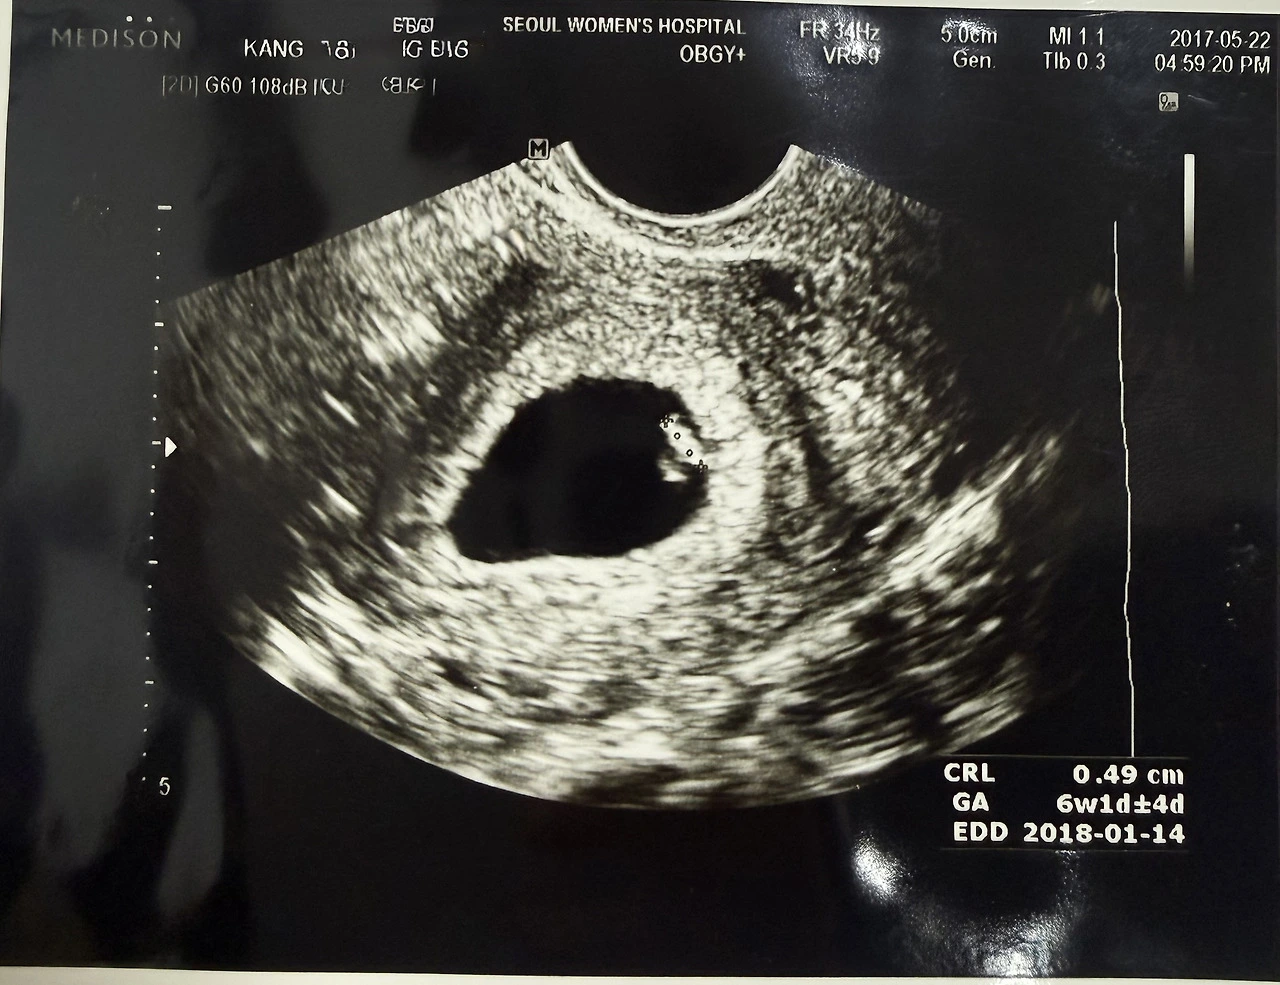

5월, 감기 기운이 있어 가까운 의원을 찾았다.

진료 후 처방약을 타고 나가려다

뒤돌아서서 카드를 다시 내밀었다.

“임신 테스트기 하나 주세요.”

화장실로 가서 테스트를 했다.

두 줄이었다.

아이의 예정일은

하이가 떠난 1월이었다.